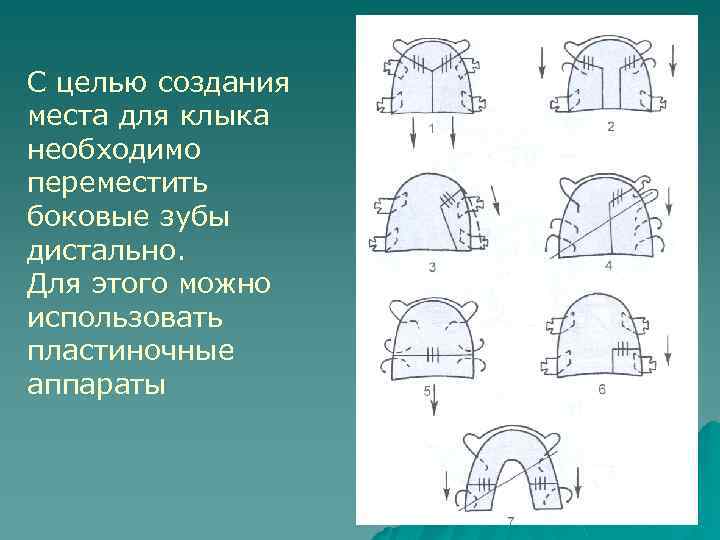

С целью создания места для клыка необходимо переместить боковые зубы дистально. Для этого можно использовать пластиночные аппараты

Аппараты 1 и 2 позволяют дистально переместить боковую группу зубов с обеих сторон. В свою очередь передние зубы перемещаются в губном направлении.

Пластиночным аппаратом 3 (пластинка на верхнюю челюсть с секторальным распилом) дистально перемещают боковые зубы

Аппарат 4 позволяет с помощью вестибулярной дуги с М -образным изгибом переместить клык дистально (конец дуги вварен в дистальную часть распила).

Аппараты 5 и 7 дистально перемещают моляры

Аппарат 6 приводит к дистальному перемещению одного моляра